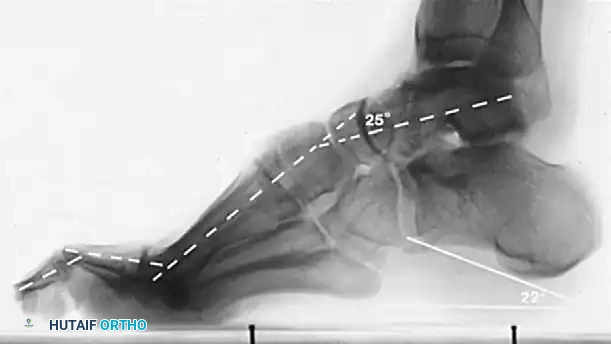

Key radiographic parameters include:

* Meary’s Angle (Talus-First Metatarsal Angle): Normally 0 degrees. In a cavus foot, the angle is increased, with the apex directed dorsally.

* Hibbs Angle: Intersection of the longitudinal axis of the calcaneus and the first metatarsal. Normal is < 45 degrees; it approaches 90 degrees in severe cavus.

* Calcaneal Pitch: Measures the degree of calcaneal deformity. Normal is 20-30 degrees.

Normal calcaneal pitch, but forefoot equinus in a patient with Charcot-Marie-Tooth disease. The calcaneal pitch angle measures the degree of calcaneus deformity.

In CMT, patients typically exhibit forefoot equinus with a relatively normal calcaneal pitch. In contrast, post-polio patients often present with a severe calcaneocavus deformity characterized by a drastically increased calcaneal pitch.